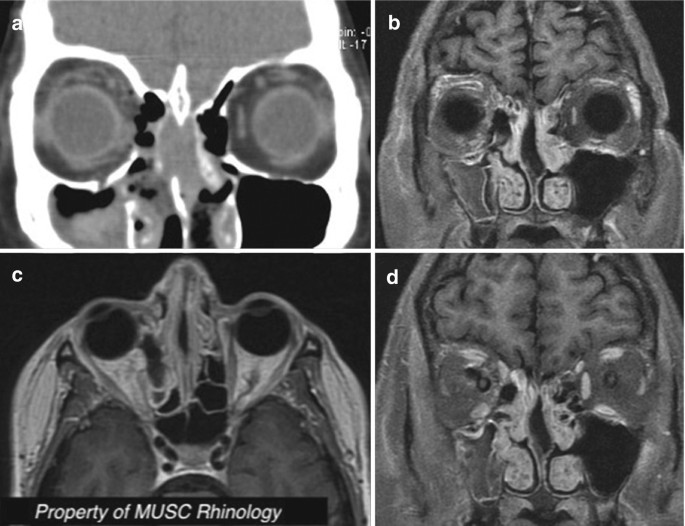

Case 2 Silent Sinus Syndrome In The Left Maxillary Sinus Preoperative Download Scientific Diagram